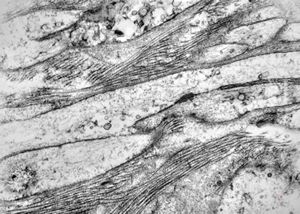

F, 39y. | collagenous and elastin fibers from corium

F,68y. | collagenous and elastin fibers from corium